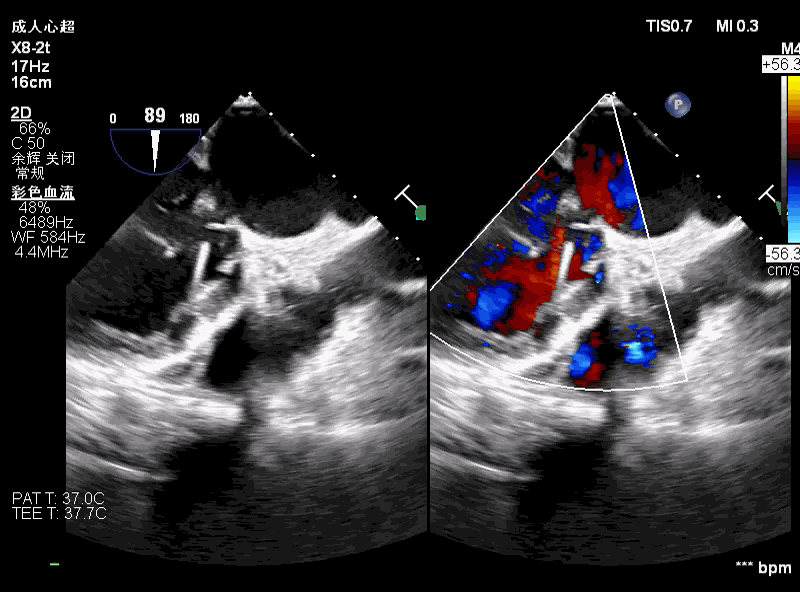

术前评估主动脉瓣可见中大量反流,二尖瓣轻微反流。

术中超声可见超硬导丝缠绕,二尖瓣大量反流,引起血压无法回升。

撤出输送器,重新调整超硬导丝大小及位置,血压回升,患者情况稳定。

超声评估,微量瓣周反流,二尖瓣工作良好,植入位置理想。